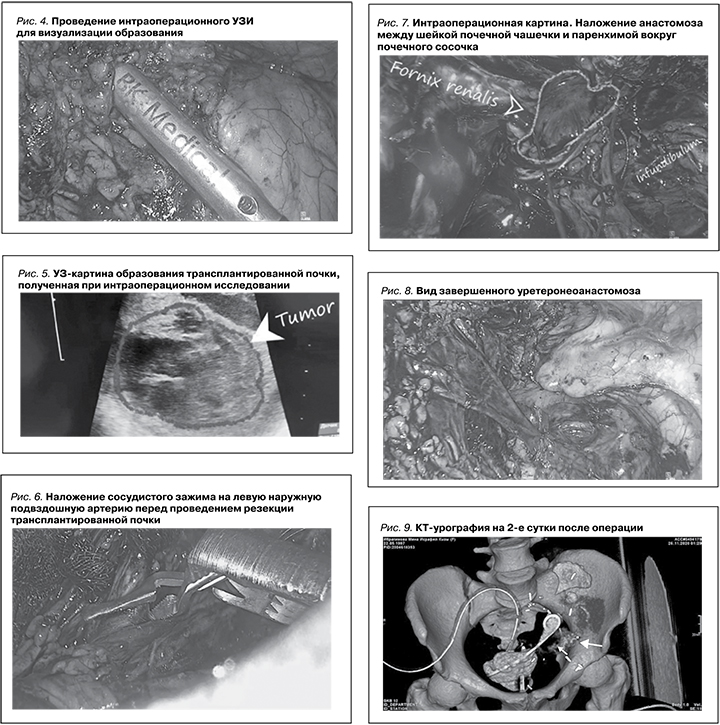

Пациентке выполнена лапароскопическая резекция почки с внутрипочечной реконструкцией мочевыводящих путей и реимплантацией мочеточника. Первым этапом проведена мобилизация почечного трансплантата, вторым – выделена правая наружная подвздошная артерия (рис. 3), взята на держалку, после мобилизации образования при помощи УЗ эндоскопического датчика (рис. 4) определены границы резекции образования (рис. 5), после пережатия наружной подвздошной артерии (рис. 6) выполнена энуклеорезекция образования, при этом отмечены линейные дефекты чашечек, а также проведена полная резекция чашечки и отдельно визуализирован почечный сосочек, отсечен мочеточник от мочевого пузыря. Малая чашечка пришита к почечному сосочку отдельными узловыми швами (рис. 7), проведено ушивание линейный дефектов чашечек. После контроля гемостаза дополнительными швами восстановлена анатомическая форма почечного трансплантата. Зажим с наружной подвздошной артерии снят, признаков кровотечения нет. Время ишемии составило 40 минут. Затем выполнен уретероцистонеоанастомоз (рис. 8). Операция завершена дренированием малого таза и брюшной полости дренажами. Время операции составило 380 минут.

Послеоперационный период протекал без особенностей. На 2-е сутки после операции выполнена КТ-экскреторная урография (рис. 9), данных за мочевой затек не было. Дренажи удалены на 5-е сутки после операции. Уровень креатинина перед операцией составил 174 мкмоль/л, в день выписки – 130. Больная выписана домой после 10 дней пребывания в стационаре.